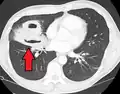

Les abcès pulmonaires sont souvent d'un seul côté et concernent les segments postérieurs des lobes supérieurs et les segments apicaux des lobes inférieurs, car ces zones dépendent de la gravité en position couchée. La présence de niveaux air-fluide implique une rupture dans l'arbre bronchique ou, rarement, la croissance d'un organisme gazogène.[réf. nécessaire]

Abcès pulmonaire à la tomodensitométrie